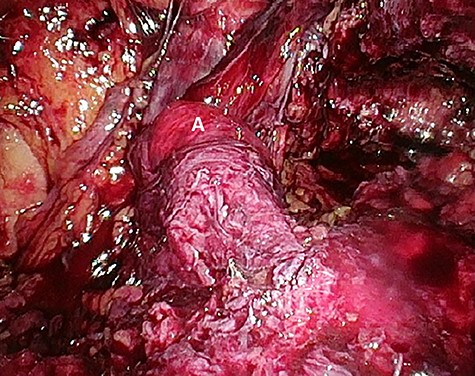

‘Loop’ of sigmoid colon in left inguinal canal (afferent loop: A; efferent loop: B; peritoneum: C).

The patient agreed to proceed with diagnostic laparoscopy for a re-re-repair of the left inguinal hernia. Intraoperatively, a loop of the sigmoid colon, which previously was hidden by colonic adhesions, was fixed into a hernia orifice lateral–caudal of the preperitoneal mesh (Fig. 4). After reopening of the peritoneum and removal of the mesh, extensive preperitoneal preparation revealed the hernia orifice located in dense scar tissue not being dissected previously (Fig. 5). A new mesh (BARD® 3D Light Mesh 12 × 17 cm) was inserted and fixed medially at the Cooper’s ligament.